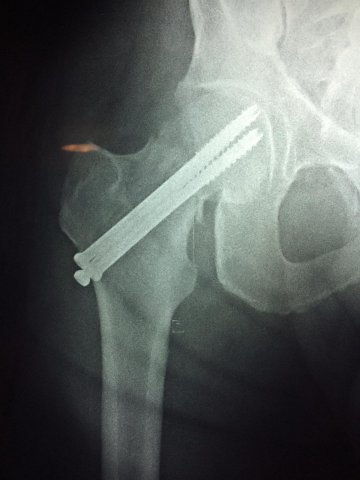

La cirugía de fractura de cadera se realiza para reparar una ruptura en la parte superior del hueso del muslo. Este hueso se denomina fémur.

Es parte de la articulación coxofemoral. Si una fractura de cadera no recibe tratamiento, es posible que deba permanecer en una silla o en la cama.